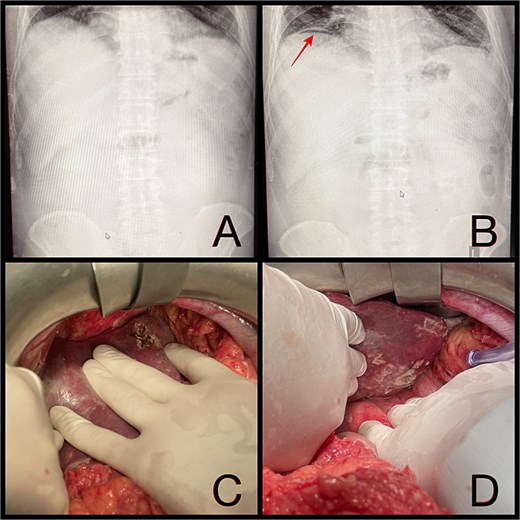

On postoperative day 14, the patient remained febrile. Computed tomography revealed a secondary abscess in segment VII (Fig. 2), which was successfully managed by percutaneous drainage under ultrasound guidance (Fig. 3). The regimen was subsequently switched to intravenous linezolid 600 mg twice daily, combined with antifungal therapy. The drains were gradually removed by postoperative day 30, while intravenous therapy continued until day 35. The patient was discharged on day 37.

(A and B) Abdominal ultrasound depicting a 9 × 5 cm abscess in segment VII. (C and D) Percutaneous drainage performed with placement of a 10 Fr catheter under ultrasound guidance.